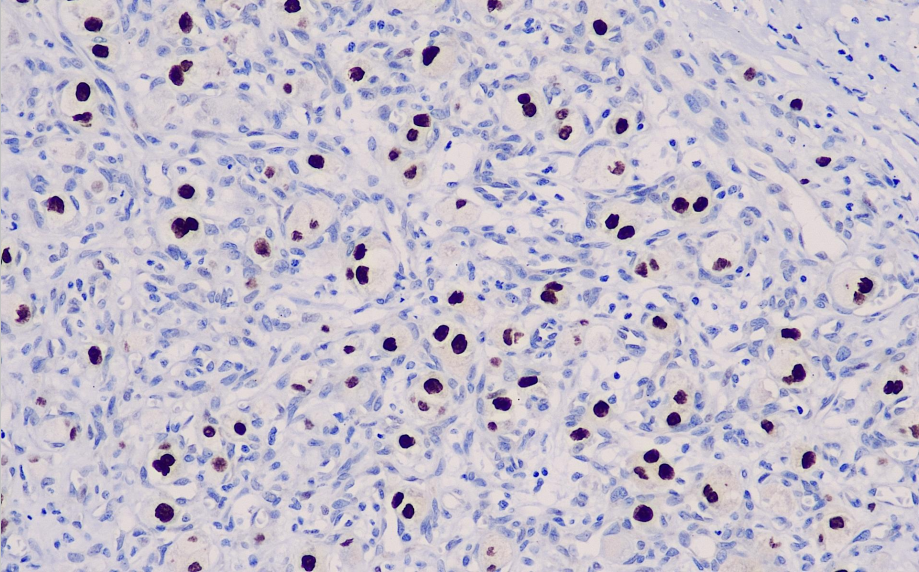

Cellular localization: nucleus

Positive control: Adenoid soft tissue sarcoma/Xp11.2 ectopic renal cell carcinoma

Ectopic renal cell carcinoma is a recently classified subtype of renal cell carcinoma, resulting from chromosomal translocation that creates a breakpoint at Xp11.2, leading to the fusion of the TFE3 transcription factor gene at this locus. Xp11 translocation renal cell carcinoma primarily affects children, with a relatively low incidence in adults. Morphologically, it is characterized by clear cytoplasm and the presence of papillary and sand-like tumor structures. Compared to typical adult renal cell carcinoma, immunohistochemical testing reveals low expression of cytokeratin (CK) and epithelial membrane antigen (EMA). For Xp11 ectopic renal cell carcinoma, the antibody with both high sensitivity and specificity is TFE3. Alveolar soft part sarcoma (ASPS) is a rare, poorly differentiated soft tissue sarcoma that primarily affects young individuals and is commonly found in the extremities. Although the rate of malignant transformation is high, ASPS patients generally have a relatively longer survival period compared to other tumors. The hallmark of ASPS is a chromosomal rearrangement at 17q25 and a gene fusion between ASPSCR1 and TFE3 at Xp11.2. It is hypothesized that these alterations lead to abnormal transcription factor activity, thereby contributing to tumorigenesis. This abnormal chimeric transcription factor retains the DNA N-terminal binding domain of TFE3 and the gene regulatory domain of ASPSCR1. Due to the hyperactive transcription factor producing a large amount of protein, it leads to the development and malignant transformation of ASPS, and also provides evidence for TFE3 as a marker for studying ASPS.

TFE3 antibody reagents can specifically bind to TFE3 molecular antigens. Immunohistochemistry kits containing TFE3 antibody reagents are suitable for the accurate diagnosis of alveolar soft part sarcoma (ASPS).